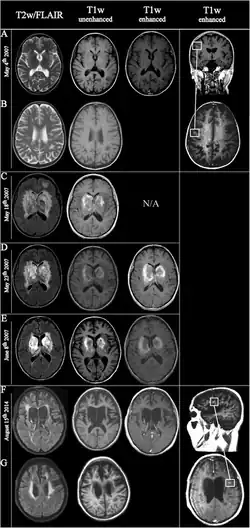

Fulminating ADEM showing many lesions. The patient survived, but remained in a persistent vegetative state